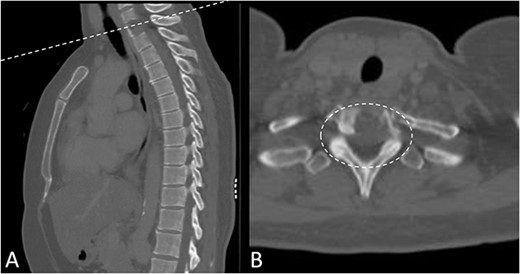

Preoperative magnetic resonance imaging (MRI) and preoperative CT scans helped determine Tokuhashi, Tomita and ESCC scores, which was vital to plan treatment for this patient (Figs 1 and 2). The occurrence of the lesion occurring in T2 indicated an anterior approach. This would be safer than a posterior approach as the ESCC grade of 2 made it surgically challenging to resect tumour and lay instrumentation around the spinal cord. An anterior approach also avoids cervico–thoracic junction fusion.

Preoperative CT Scan December 2019. Sagittal view of oligometastatic lesion at T2 vertebral body. (A) Sagittal view of oligometastatic lesion at T2 vertebral body. (B) Transverse view determined ESCC grade 2 as there is spinal cord compression, but with cerebrospinal fluid visible around the cord.